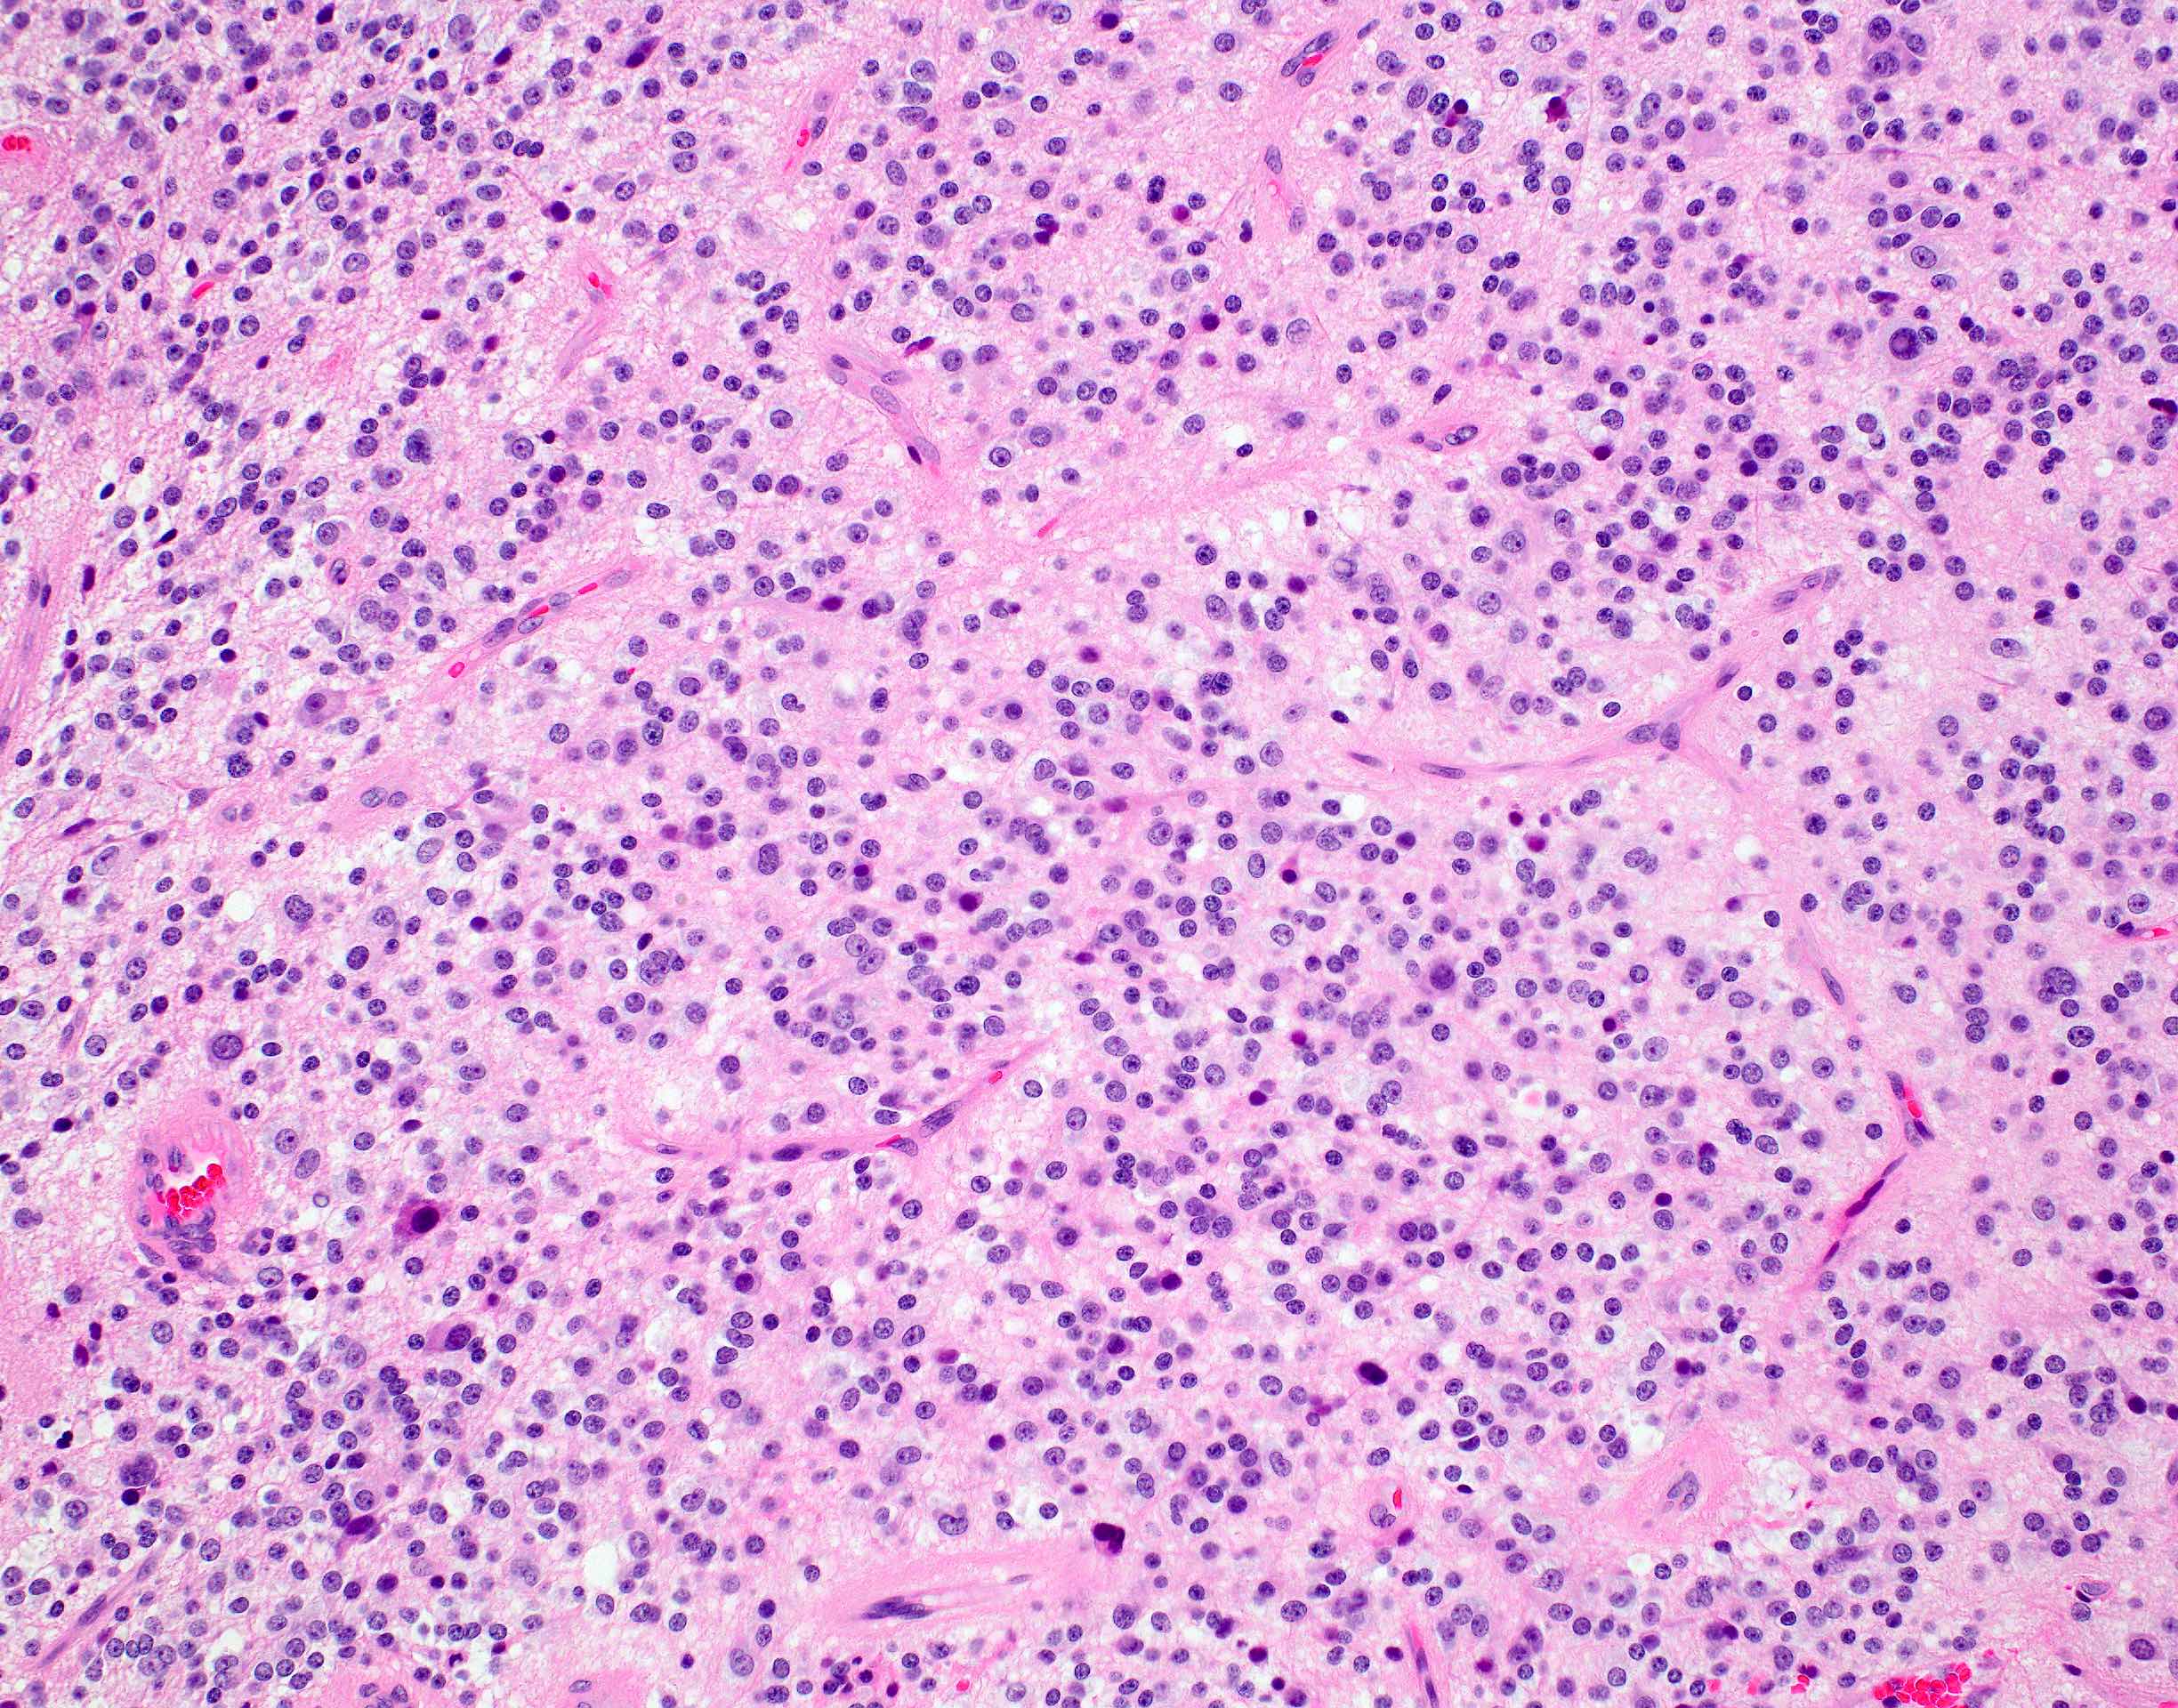

Microscopic (histologic) description

- Closely packed cells with small, round, monotonous nuclei (slightly larger than a normal oligodendrocyte)

- Perinuclear clearing (fried egg appearance)

- Formalin fixation artifact

- Will not be seen on frozen sections or smear preparations

- Network of thin walled, branching blood vessels (chicken wire vasculature)

- Microcalcifications (calcospherites) are characteristic

- Presence of perineural, perivascular or subpial aggregates of tumor cells (secondary structures of Scherer)

- Occasional mitoses and moderate nuclear atypia are still consistent with grade 2 designation (J Neuropathol Exp Neurol 2001;60:248)

- Features of CNS WHO grade 3 oligodendroglioma:

- Presence of microvascular proliferation

- Presence of necrosis

- Presence of brisk mitotic activity

- Strict mitotic figure cutoffs do not currently exist; some authors suggest ≥ 6 mitoses per 10 high power fields for WHO grade 3 designation in tumors without necrosis or vascular proliferation (Neuro Oncol 2014;16:1244, Neuro Oncol 2016;18:888)

Microscopic (histologic) images

Contributed by Jared T. Ahrendsen, M.D., Ph.D. and John DeWitt, M.D., Ph.D.